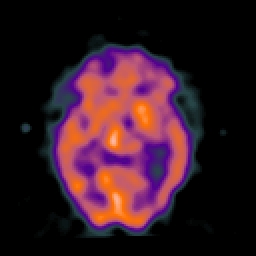

SPECT TC Study #6 -- Slice #25

[Home][Help][Clinical][Tour 1][Tour 2][Tour 3] Slice 25